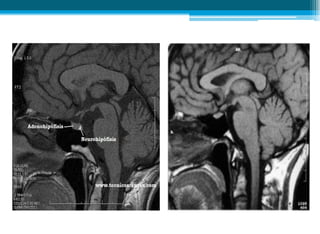

• Resonancia magnética pediátrica de silla turca

(hipófisis):

▫ Engrosamiento del tallo hipofisario y ausencia de

señal propia de neurohipófisis, acordes con la

clínica referida de diabetes insípida.

• Resonancia magnéticapediátrica de silla turca (hipófisis): ▫ Engrosamiento del tallo hipofisario y ausencia de señal propia de neurohipófisis, acordes con la clínica referida de diabetes insípida.